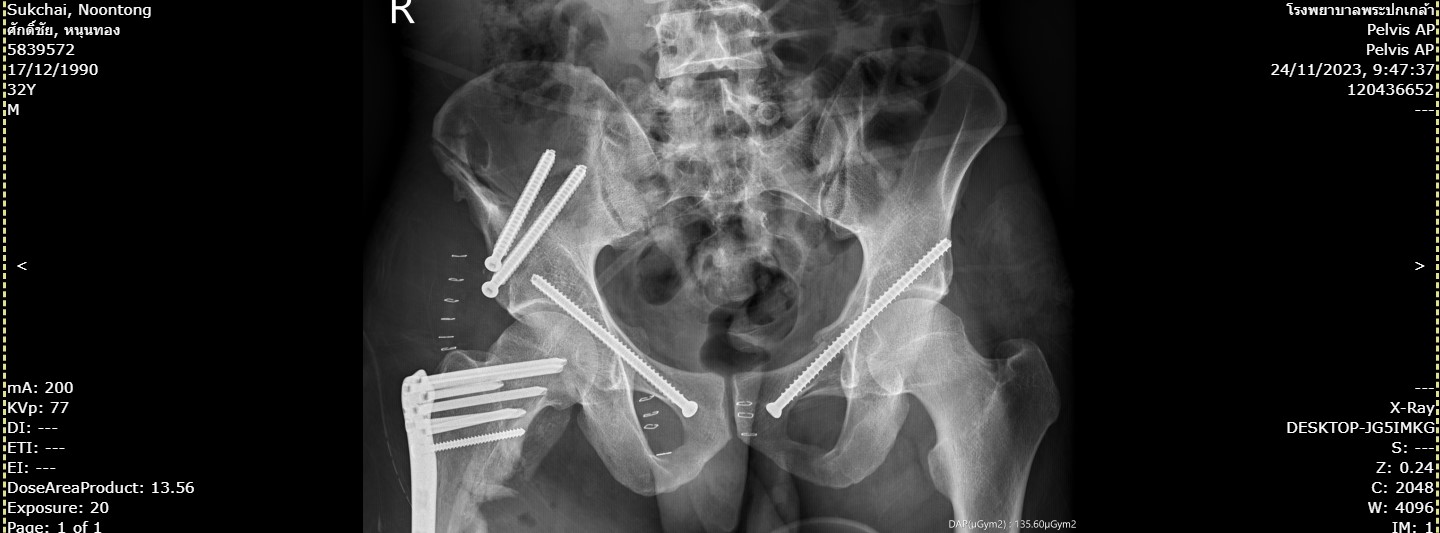

135ศักดิ์ชัย.jpg                 17-Apr-2024 01:16              125927